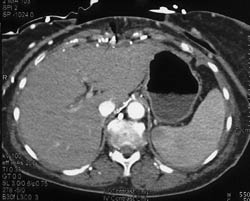

Hot Spot Liver Due to SVC Occlusion